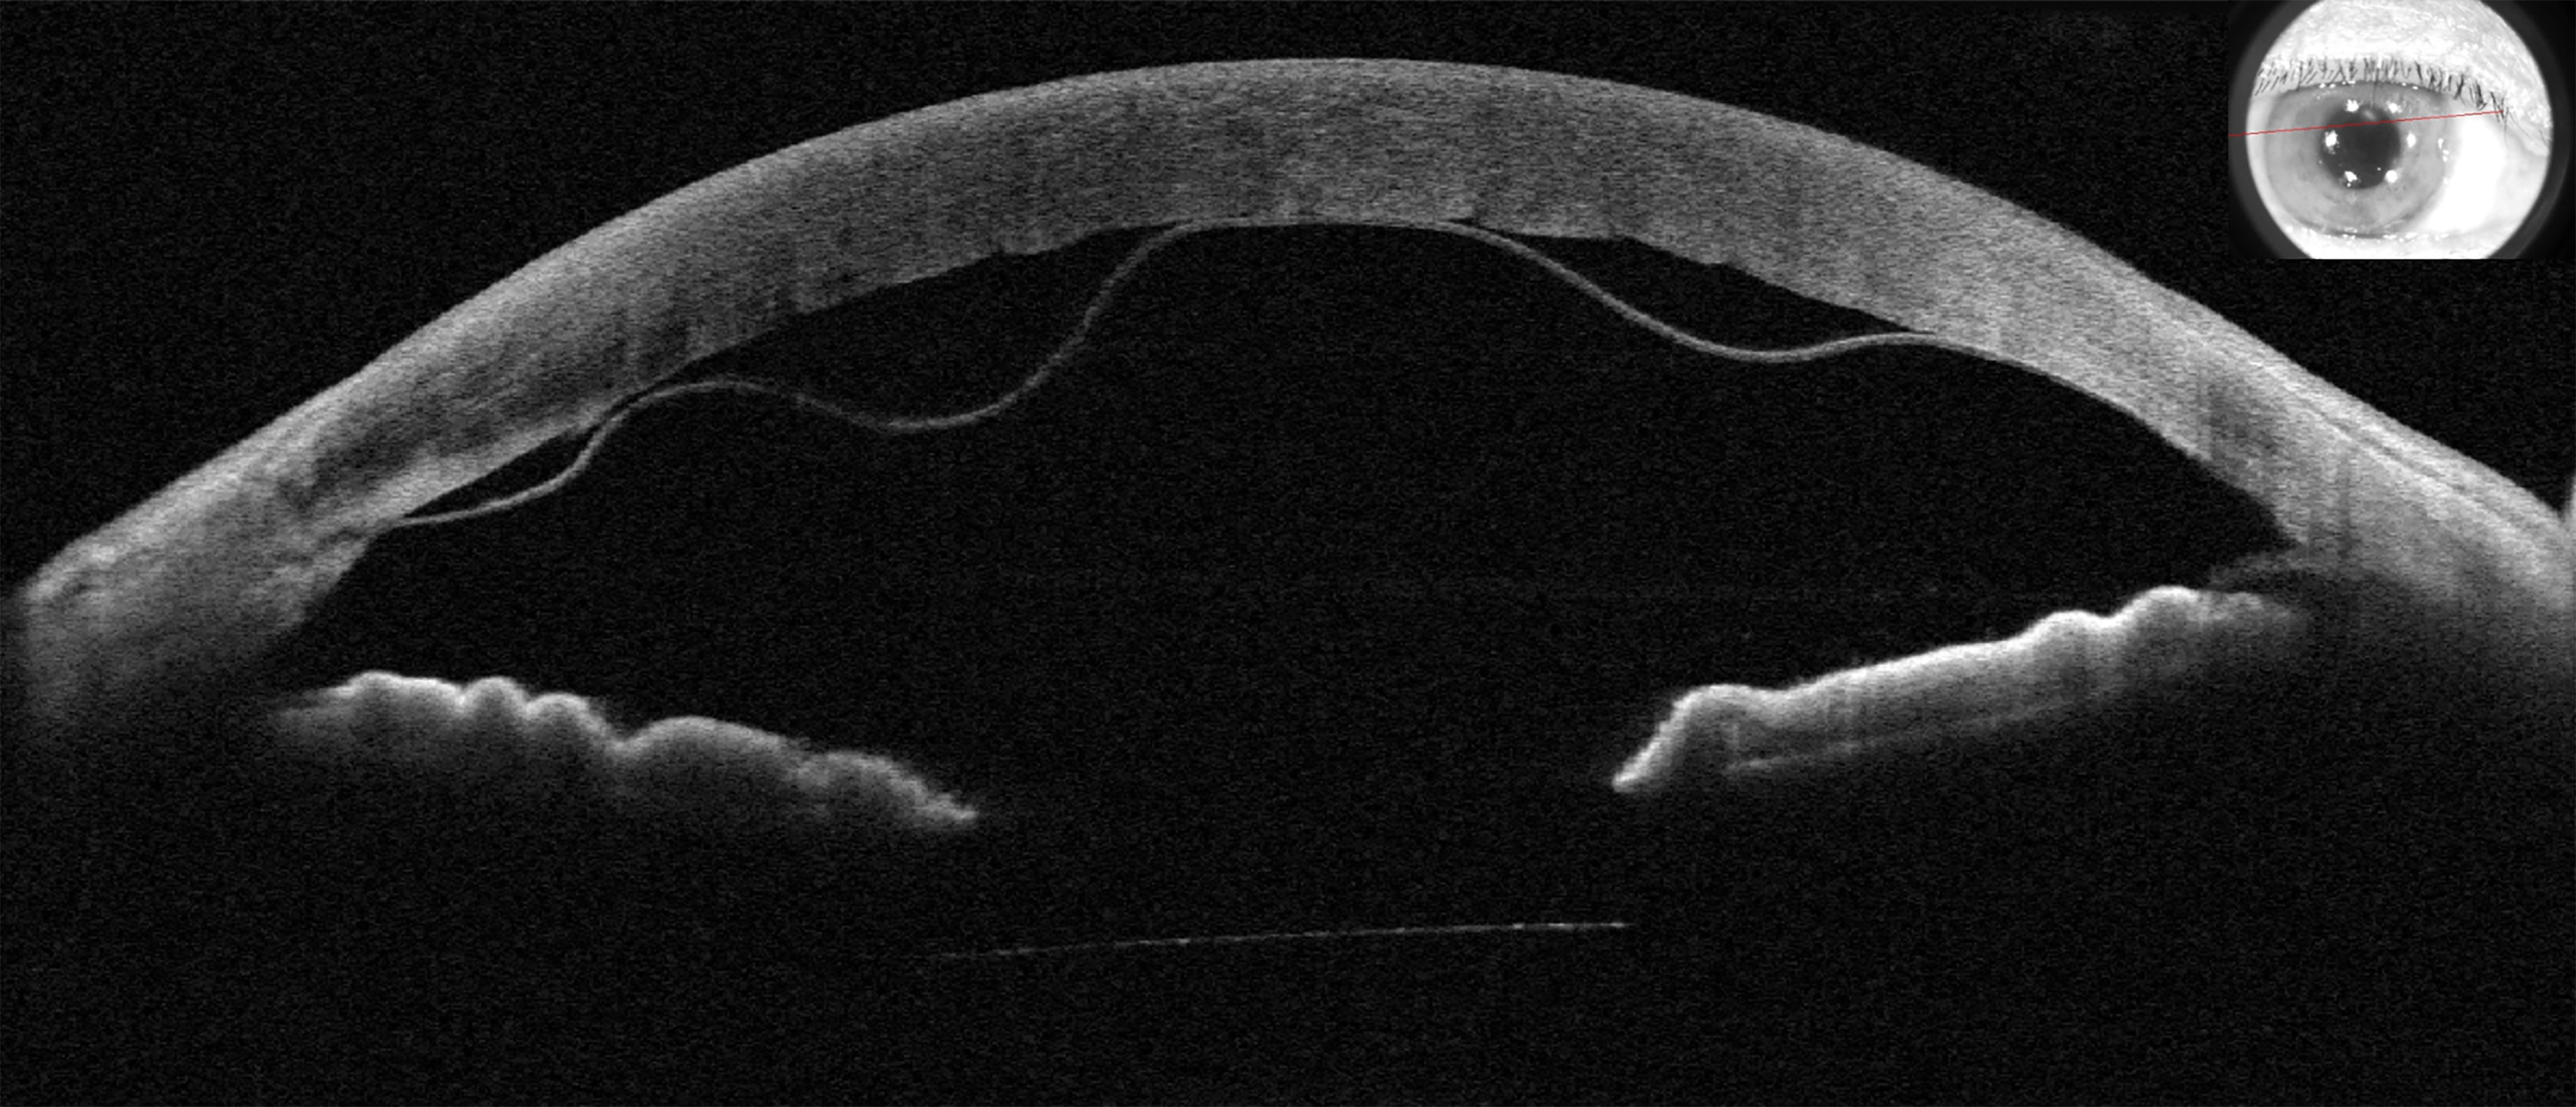

Descemet Membrane Detachment Presented by Chitaranjan Mishra This photograph received Honorable Mention, Ocular Coherence Tomography in the 2025 OPS Scientific Exhibit. Filed Under Retina OPS Photo